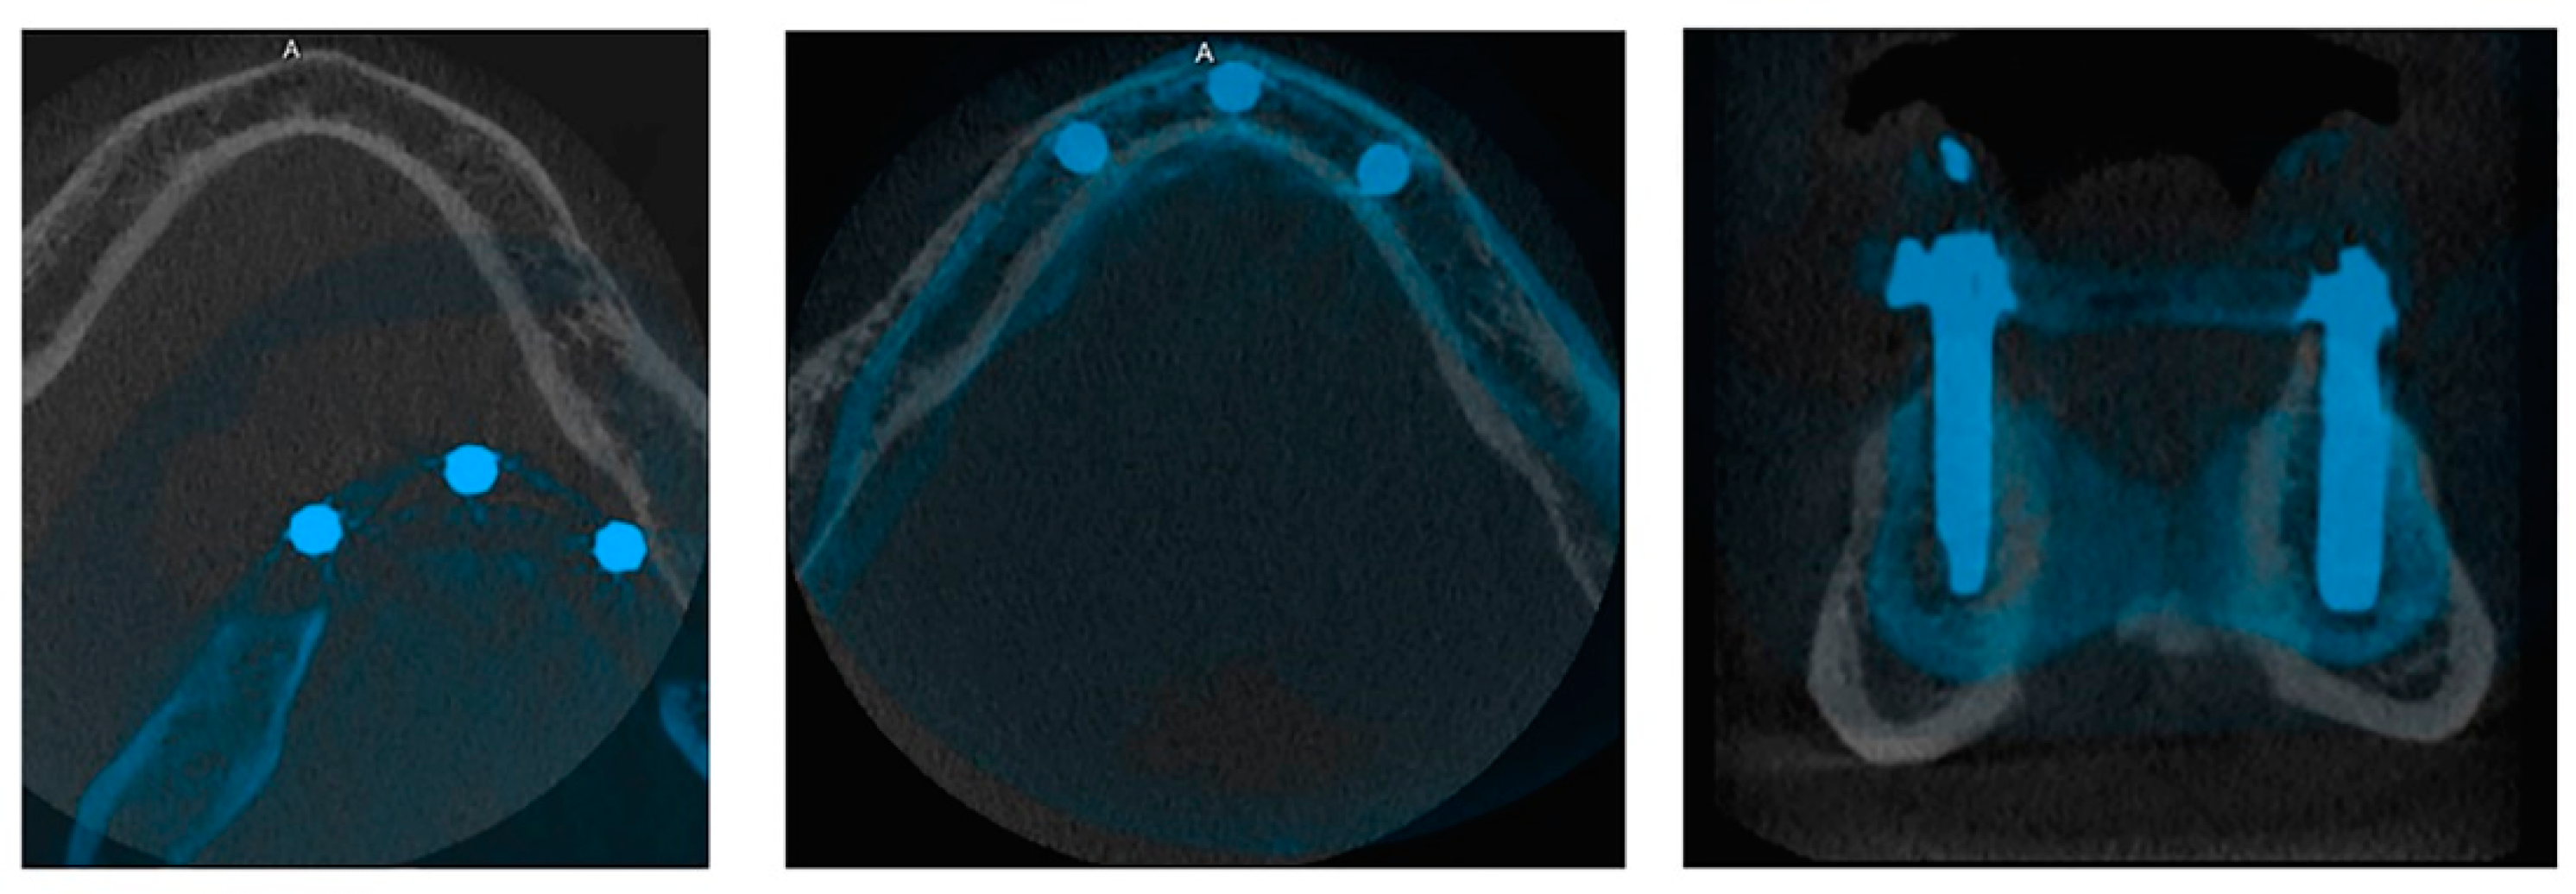

2. Materials and Methods

2.1. Study Design